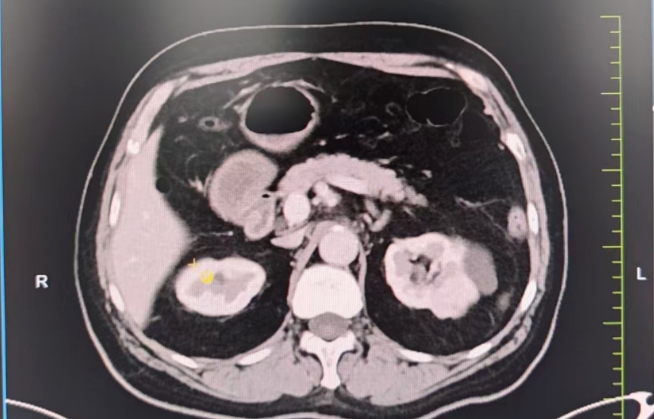

生死抉擇:心臟術(shù)后又遇腎腫瘤,求醫(yī)之路一波三折。3年前,劉大爺因嚴重冠心病接受了心臟搭橋手術(shù),并置換主動脈瓣生物瓣。術(shù)后長期服用阿司匹林抗凝,病情相對穩(wěn)定。然而半年前,一次體檢發(fā)現(xiàn)他的左腎長出一枚直徑3×2cm的腫瘤,需盡快手術(shù)切除。

難題接踵而至 1.保腎難題:劉大爺保腎臟意愿強烈,需行高難度的腹腔鏡腎部分切除術(shù),但因劉大爺心臟術(shù)后長期口服阿司匹林抗凝,對于保腎手術(shù)增加了出血風險高。2.心臟高風險:多家醫(yī)院評估后認為,劉大爺心臟功能較差(心功能Ⅱ級),術(shù)中可能出現(xiàn)心衰、血栓等致命風險,拒絕手術(shù)。

兩大難關(guān),精準突破1. 心臟“護航”計劃:由醫(yī)院副院長、心血管中心主任隋立有牽頭,調(diào)整抗凝方案:術(shù)前7天停用阿司匹林,改用低分子肝素橋接,降低術(shù)中出血風險。優(yōu)化心臟功能:控制血壓,確保心功能穩(wěn)定在Ⅱ級。術(shù)中全程心電監(jiān)護,實時調(diào)控血壓、心率,預防心肌缺血。 2. 保腎“微創(chuàng)”方案:泌尿外科團隊在張寶主任的帶領(lǐng)下決定采用后腹腔鏡下腎部分切除術(shù),最大限度保留正常腎組織,術(shù)中控制出血量<50ml,手術(shù)時間縮短至1.5小時,大幅降低心臟負荷,術(shù)后轉(zhuǎn)入重癥監(jiān)護室(ICU)密切監(jiān)測,24小時專人監(jiān)護心肺功能。